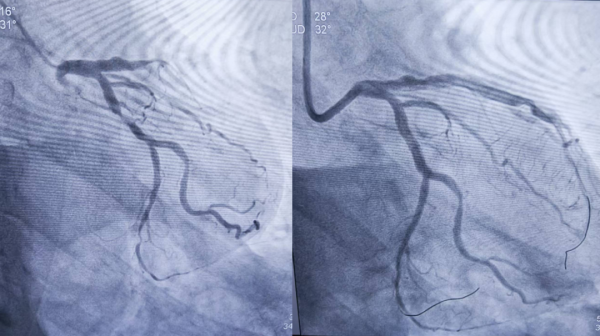

1、39岁男性,前降支闭塞,行血栓抽吸+冠脉内溶栓。

2、71岁男性,右冠闭塞,行药物球囊扩张成形术。

3、69岁男性,双支病变,行介入治疗。

包括冠脉介入、结构性心脏病介入、电生理介入、大血管及外周血管介入、心脏瓣膜介入等。